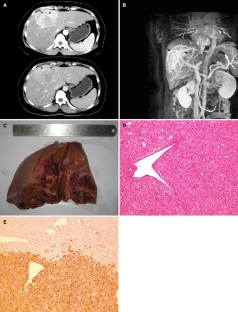

Fig. 1